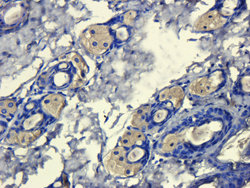

- Submitted by

- antibodies-online (provider)

- Main image

- Experimental details

- IHC